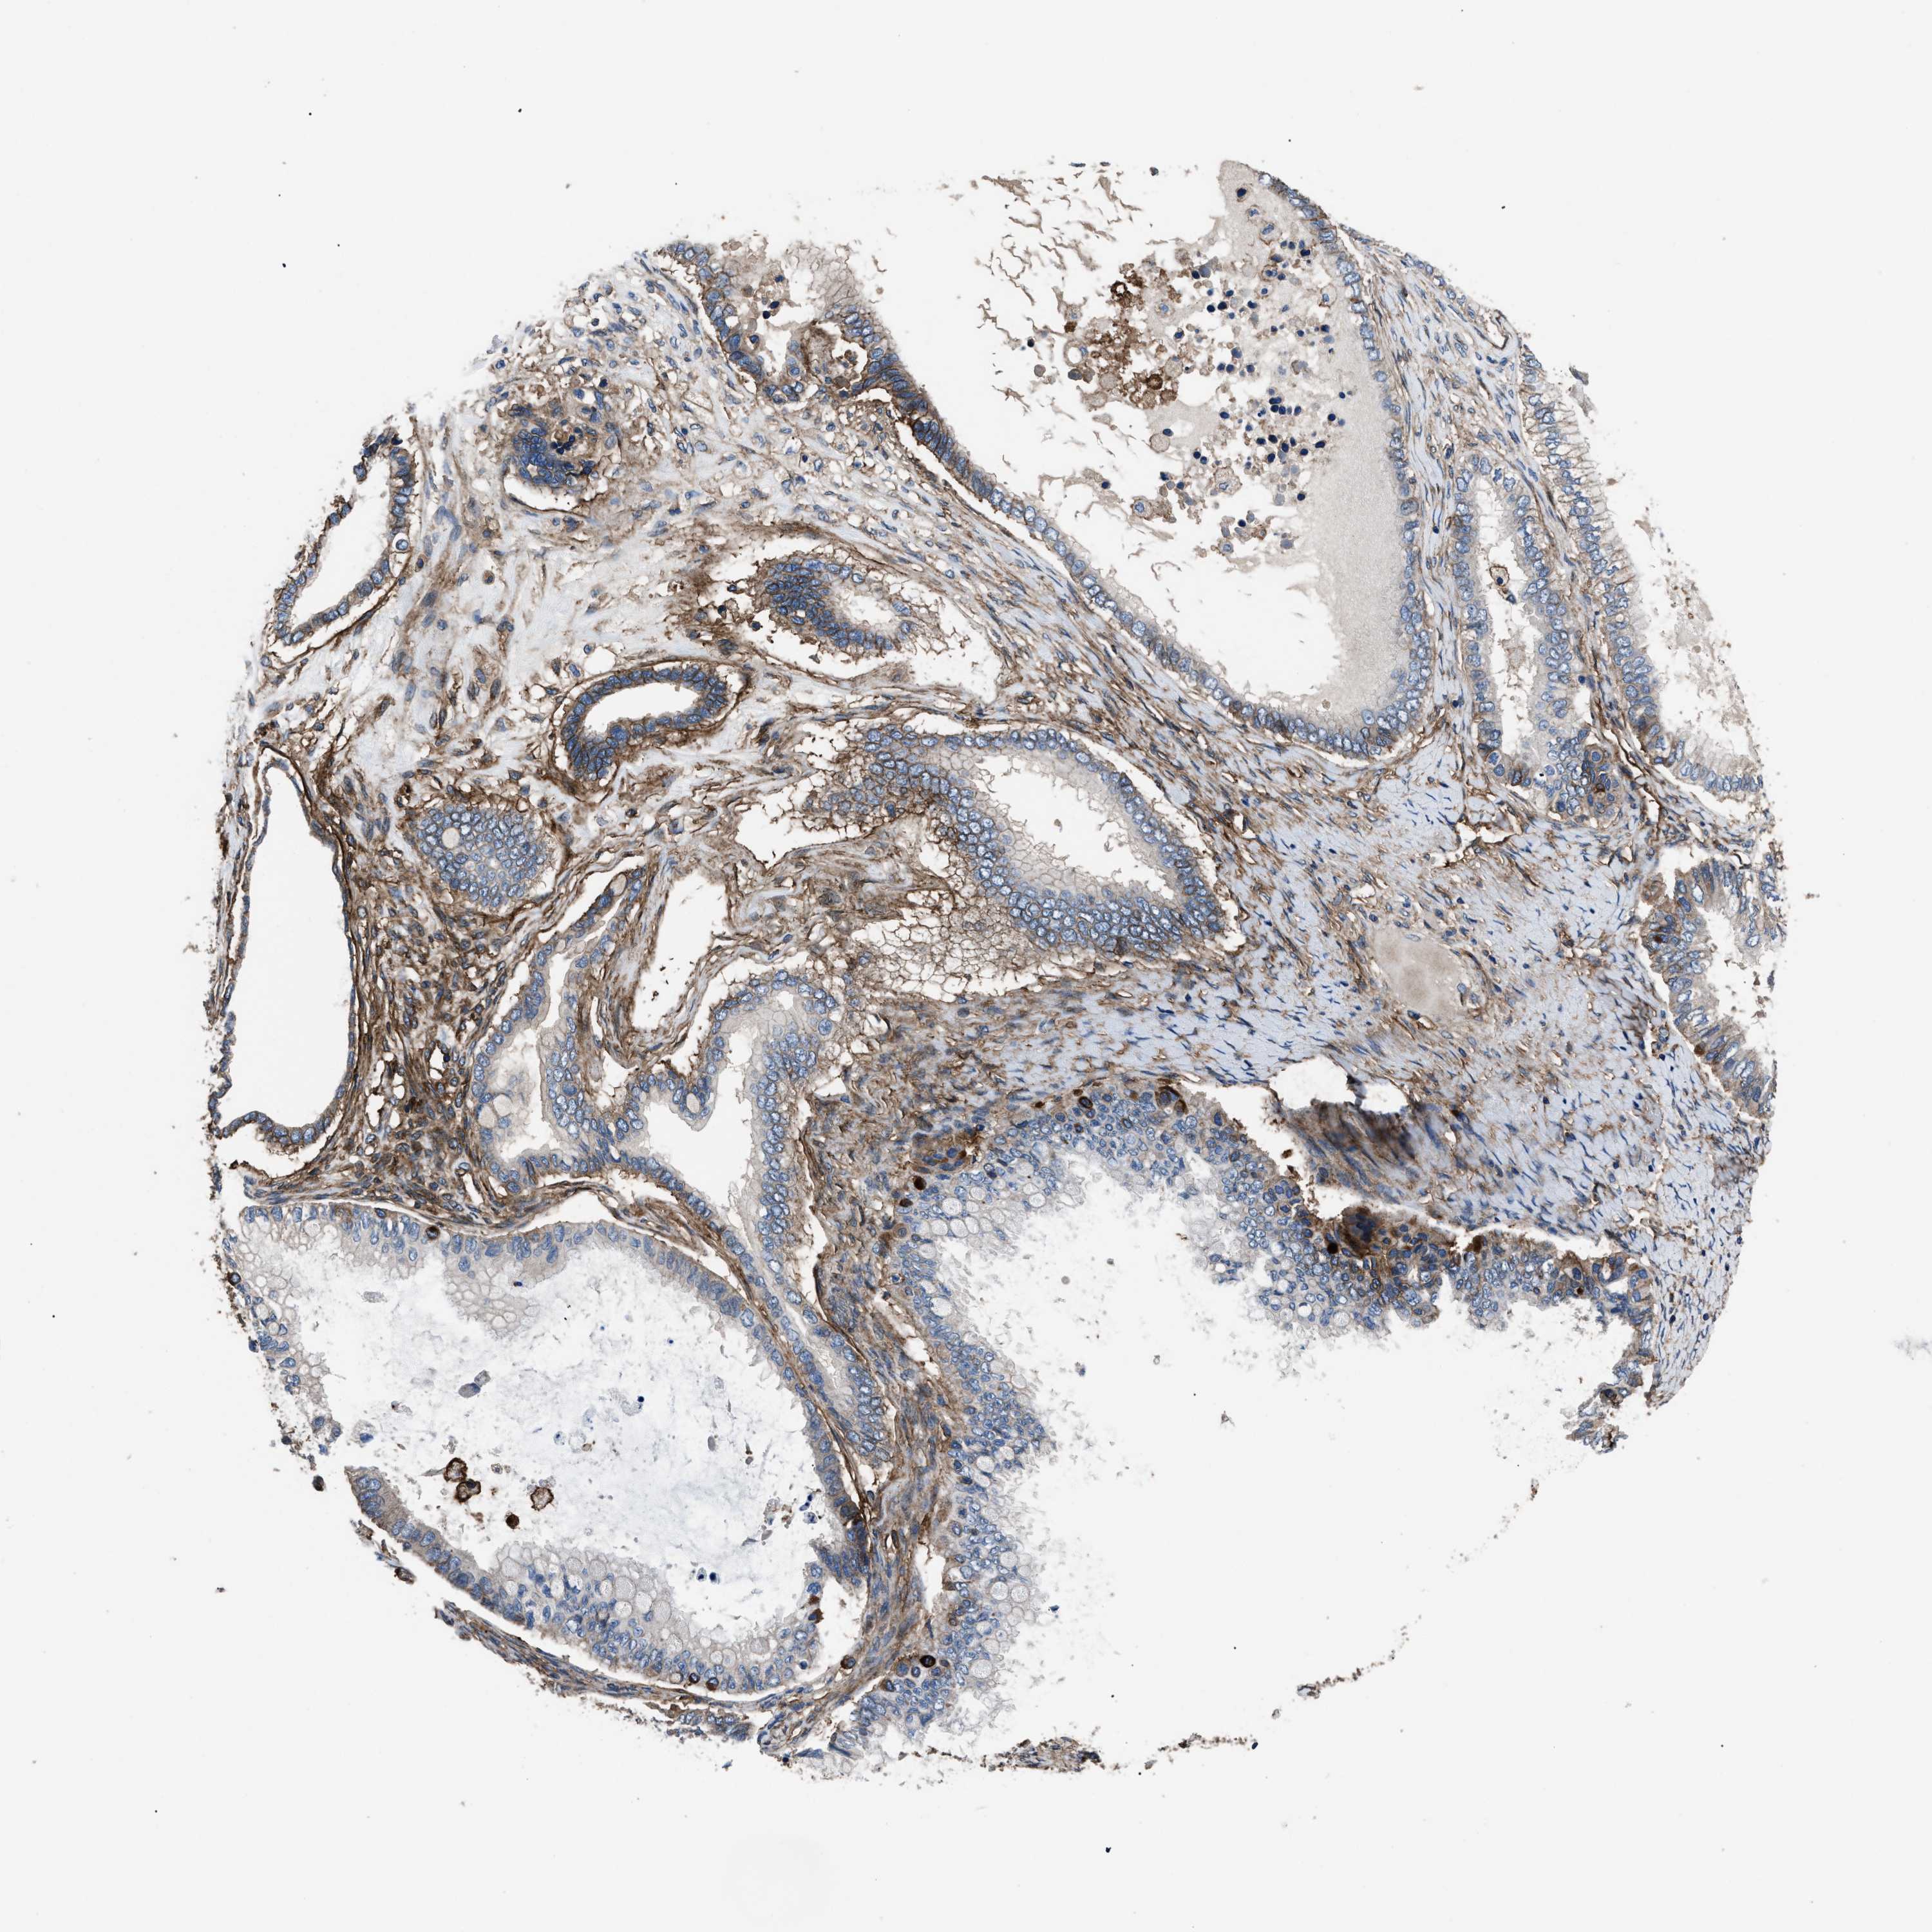

OVARIAN CANCER - Protein expressioni

A mouse-over function shows sample information and annotation data. Click on an image to view it in a full screen mode. Samples can be filtered based on level of antibody staining by selecting one or several of the following categories: high, medium, low and not detected. The assay and annotation is described here.

Note that samples used for immunohistochemistry by the Human Protein Atlas do not correspond to samples in the TCGA dataset.

Antibody stainingi

Antibody staining in the annotated cell types in the current human tissue is reported as not detected, low, medium, or high, based on conventional immunohistochemistry profiling in selected tissues. This score is based on the combination of the staining intensity and fraction of stained cells.

Each image is clickable and will lead to virtual microscopy that enables deeper exploration of all samples and also displays staining intensity scores, fraction scores and subcellular localization as well as patient and tissue information for each sample.

Antibody HPA009285

Antibody HPA017139

Antibody CAB017826

Cystadenocarcinoma, serous, NOS

Carcinoma, endometroid

Cystadenocarcinoma, mucinous, NOS

Carcinoma, NOS